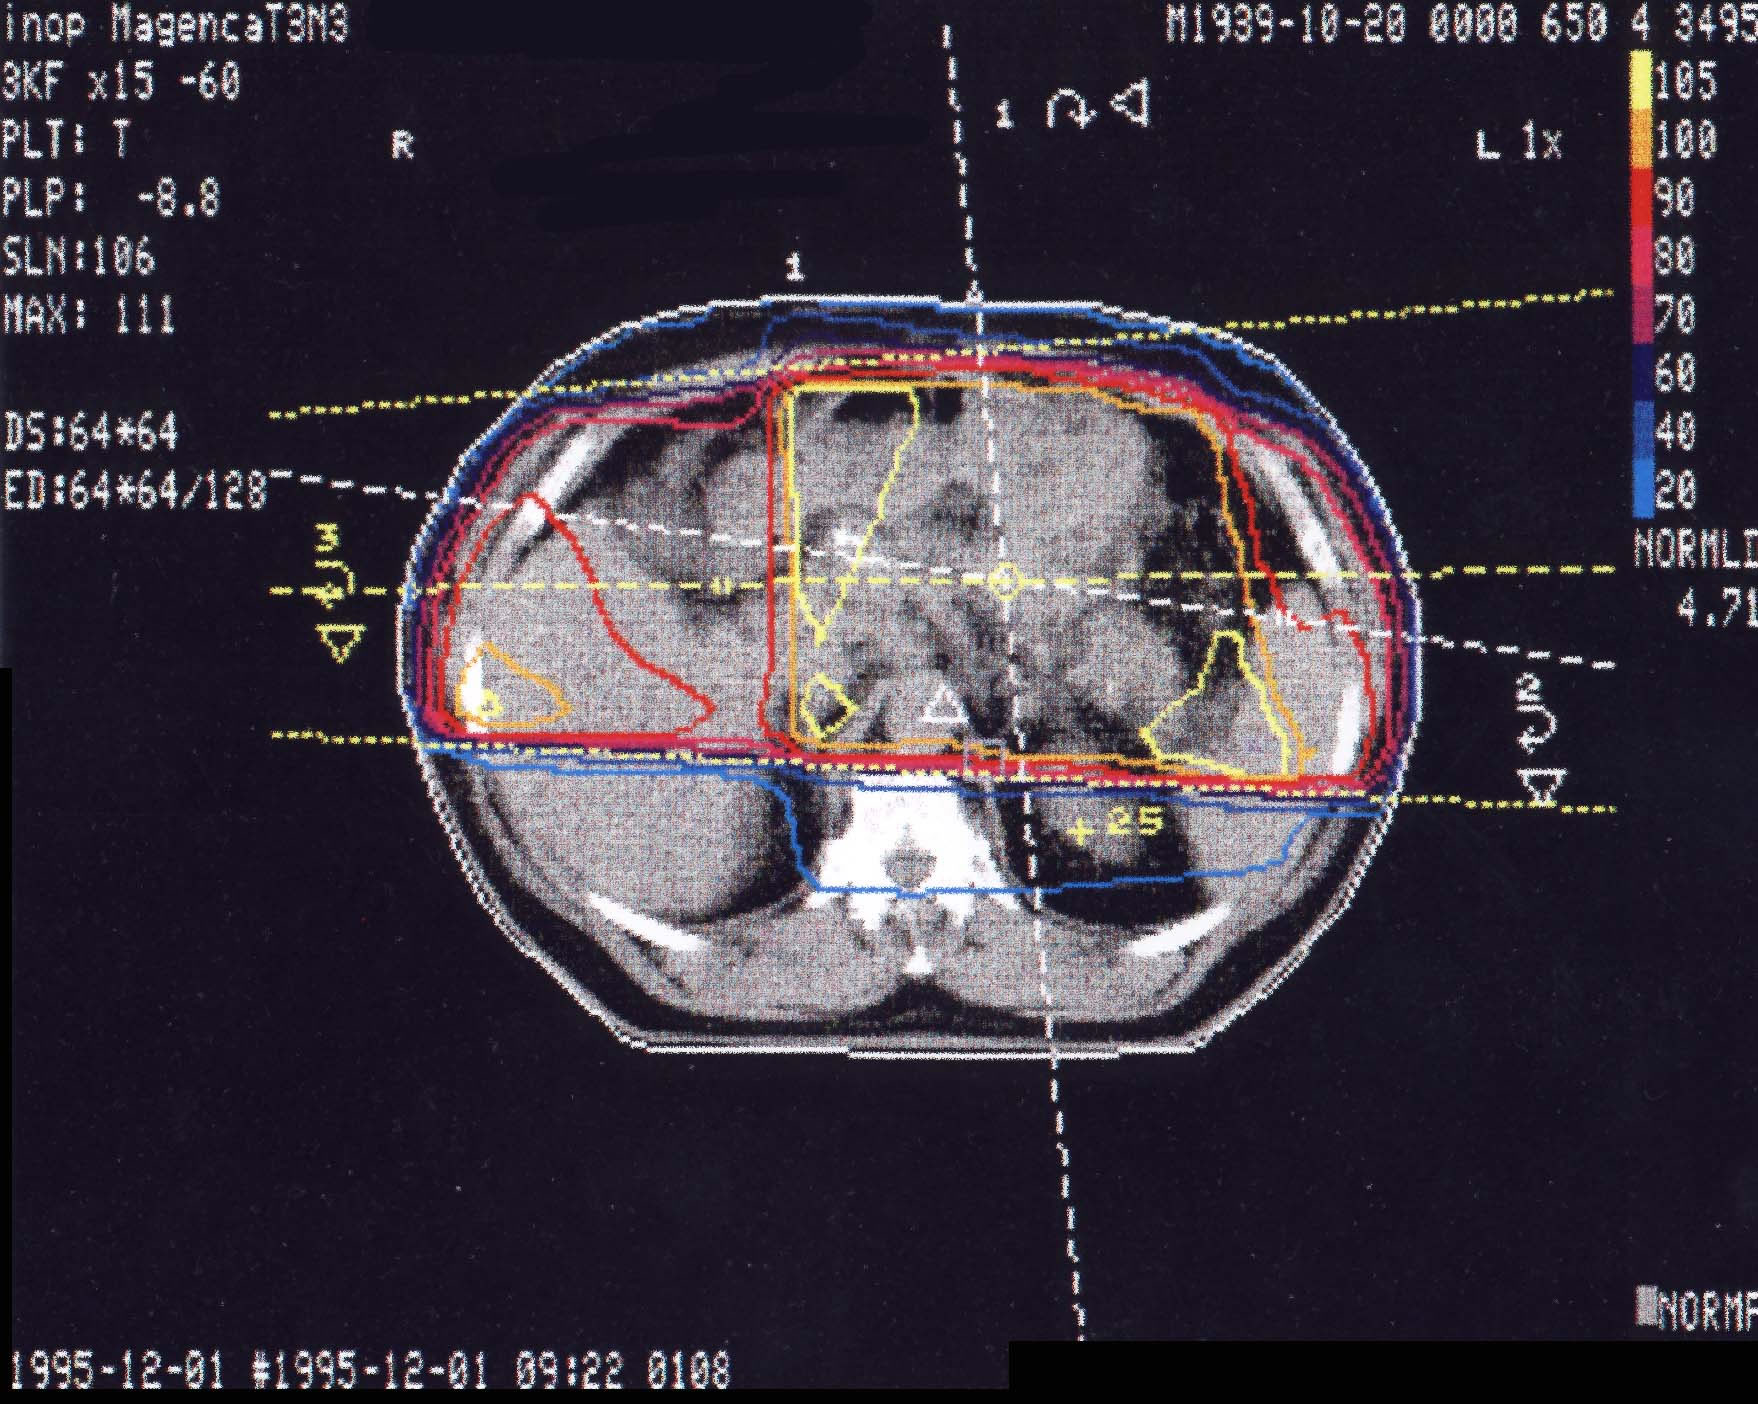

Tumore des Magens: Bestrahlungsplan